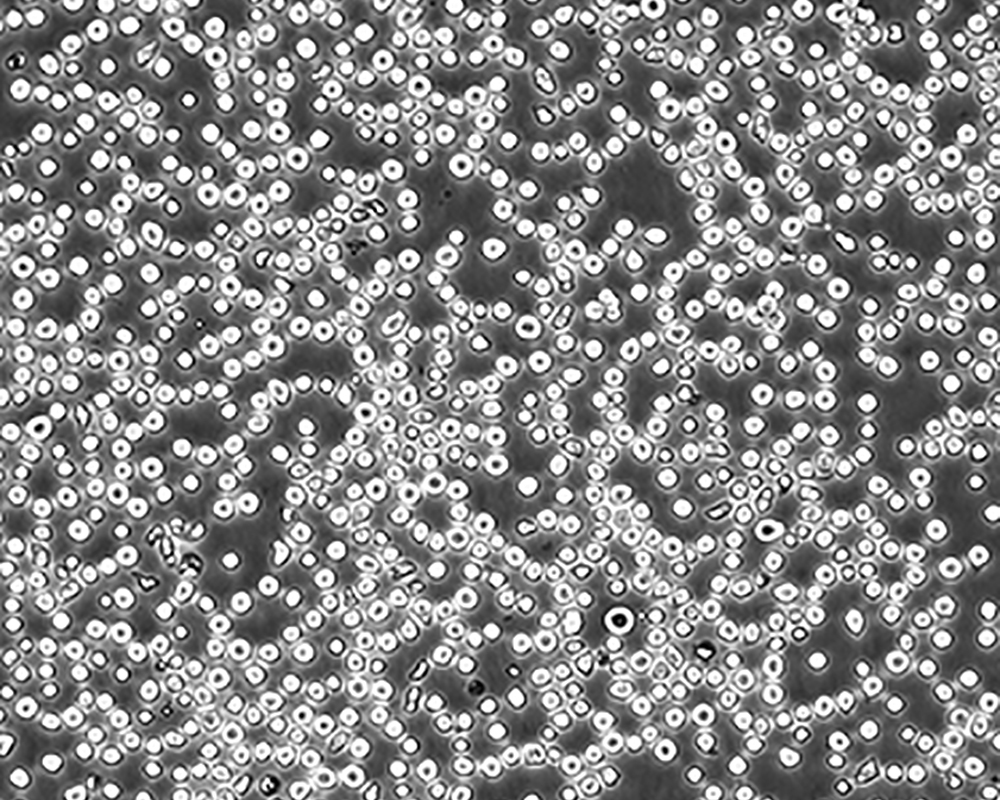

生長特性 suspension

形態(tài)特征 lymphoblast

細(xì)胞描述 CEM/C1是人T細(xì)胞白血病細(xì)胞株CCRF-CEM(見ATCC CCL-119)具有喜樹堿抗性的衍生株。1991年細(xì)胞株選擇并亞克隆了對CPT的抗性。細(xì)胞表現(xiàn)出對CPT類似物水溶性的托泊替康和非水溶性的9-氨基-CPT及10,11-亞甲二氧基-CPT具有交叉抗性。CEM/C1細(xì)胞對CPT的敏感性較母系CEM細(xì)胞低31倍。CEM/C1細(xì)胞表現(xiàn)非典型的多藥抗性和轉(zhuǎn)換拓補(bǔ)異構(gòu)酶I催化活性。對CPT的抗性維持6個月以上。